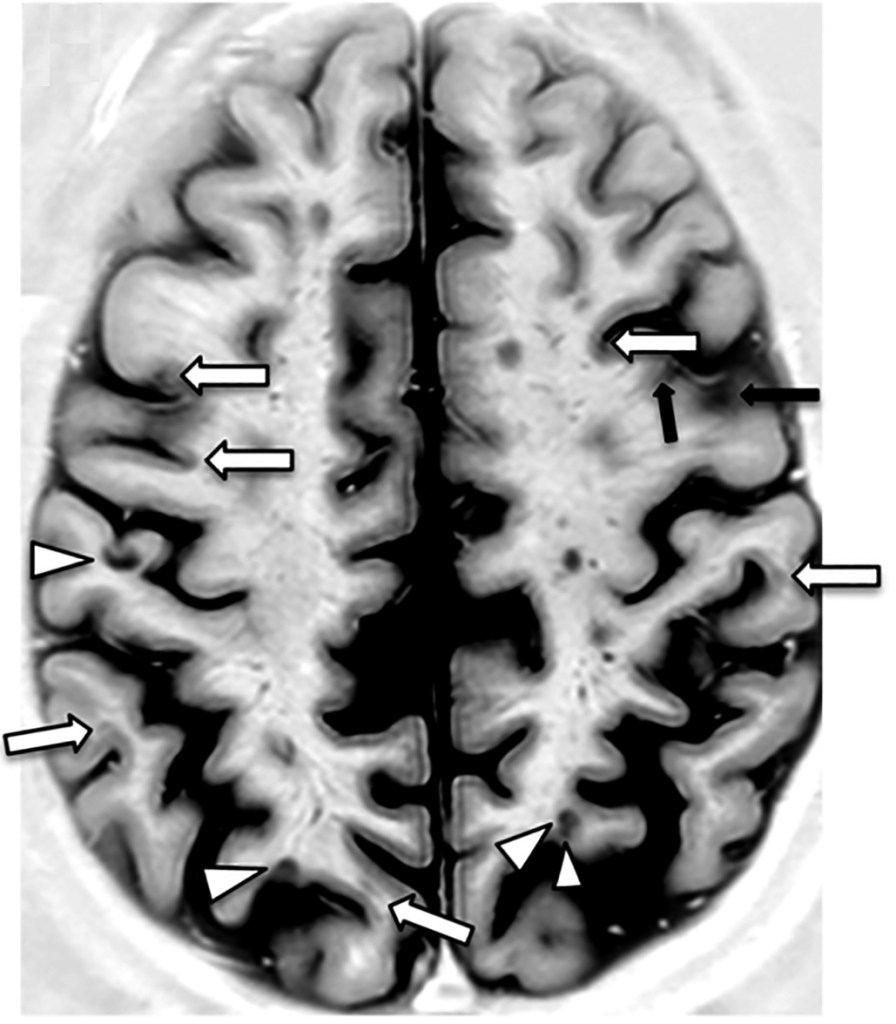

The case study examined the experiences of a 29-year-old female showing various MS symptoms, including impaired coordination, dizziness, and slurred speech. These symptoms had begun a day after the patient received the hepatitis B and flu vaccine and persisted for six days, with symptoms progressively worsening. The patient’s vitals and lab results displayed no abnormalities. However, a CT scan of the head indicated multifocal lesions, an attribute of tumefactive MS. Further, MRI of the brain revealed lesions in the bilateral cerebral and left cerebellar hemisphere with edema. Researchers also discovered macrophages and lymphocyte infiltrates as well as gliosis and loss of myelin in the patient. After the patient was treated with plasmapheresis, a process where blood is taken out from the body to be separated into components, the patient’s condition improved immediately. For the next two years, the patient experienced no further neurological disturbances or lesions.

[2] Image retrieved from: https://commons.wikimedia.org/wiki/File:Axial_PSIR_MRI_of_a_brain_with_multiple_sclerosis_lesions.jpg